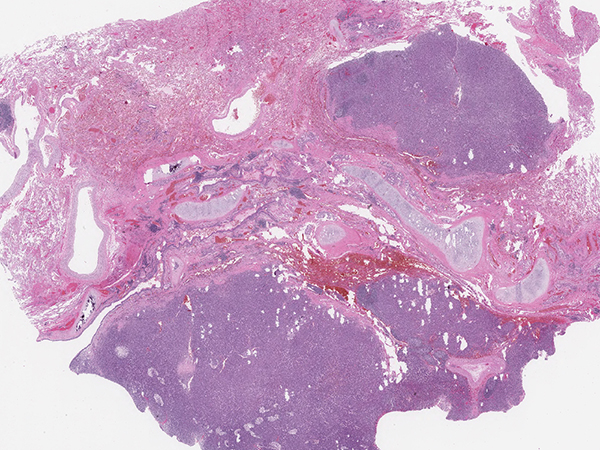

Clinical History: A 66-year-old woman, never-smoker, with a remote history of breast cancer presented with a fall and was found to have a lung mass on chest X-ray. PET/CT scan of the chest showed a 4.7 cm heterogeneous and partially calcified right upper lobe mass which was FDG avid (Figure 1). H&E sections of the resection specimen showed a well-circumscribed neoplasm associated with an airway (Figure 2). The tumor was composed of plump epithelioid to spindled cells with pale cytoplasm and relatively bland ovoid nuclei. Scattered cells showed hyperchromatic multilobated nuclei (Figure 3) but there was no increased mitotic activity. A rich network of capillaries and a few dilated hemangiopericytoma-like blood vessels were present (Figure 4). The stroma contained a prominent inflammatory infiltrate composed of lymphocytes, clusters of foamy macrophages and scattered eosinophils. Periodic acid-Schiff (PAS) stain highlighted prominent cytoplasmic glycogen (Figure 5). Immunohistochemical stains showed the neoplastic cells were positive for TFE3 (Figure 6) and negative for all other markers tested (including pan-cytokeratin, TTF-1, ERG, smooth muscle actin, HMB45, S100, GATA3, PAX8, TLE1, CD35, CD21, estrogen receptor, STAT6 and ALK-1). The tumor was sent for RNA fusion analysis using the Archer DX solid tumor gene fusion panel, which revealed a YAP1-TFE3 fusion.

This case illustrates an example of clear cell stromal tumor of the lung (CCST-L), previously termed hemangiopericytoma-like clear cell stromal tumor, a rare mesenchymal tumor of the lung recently reported to harbor YAP1-TFE3 gene fusions. A small number of cases have been described in the literature, predominantly in adult patients presenting with a solitary lung nodule. Grossly the tumor appears well-circumscribed and arises in close proximity to the bronchial tree. On microscopic examination, the tumor comprises a solid or nested proliferation of epithelioid to spindled cells with clear, pale or eosinophilic cytoplasm and ovoid nuclei. Scattered atypical cells with hyperchromatic, multilobated nuclei may be seen, but overall there is minimal cytologic atypia and no increased mitotic activity. The stroma is vascular with a rich capillary network and thick-walled hemangiopericytoma-like vessels. By immunohistochemistry, the tumor shows positive staining for TFE3 and vimentin, while other markers are negative. Notably, the immunoprofile of CCST-L is distinct from conventional hemangioblastoma (associated with von Hippel -Lindau disease), which expresses S100 and inhibin.